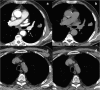

Radiomics is an emerging translational field of research aiming to extract mineable high-dimensional data from clinical images. The radiomic process can be divided into distinct steps with definable inputs and outputs, such as image acquisition and reconstruction, image segmentation, features extraction and qualification, analysis, and model building. Each step needs careful evaluation for the construction of robust and reliable models to be transferred into clinical practice for the purposes of prognosis, non-invasive disease tracking, and evaluation of disease response to treatment. After the definition of texture parameters (shape features; first-, second-, and higher-order features), we briefly discuss the origin of the term radiomics and the methods for selecting the parameters useful for a radiomic approach, including cluster analysis, principal component analysis, random forest, neural network, linear/logistic regression, and other. Reproducibility and clinical value of parameters should be firstly tested with internal cross-validation and then validated on independent external cohorts. This article summarises the major issues regarding this multi-step process, focussing in particular on challenges of the extraction of radiomic features from data sets provided by computed tomography, positron emission tomography, and magnetic resonance imaging.